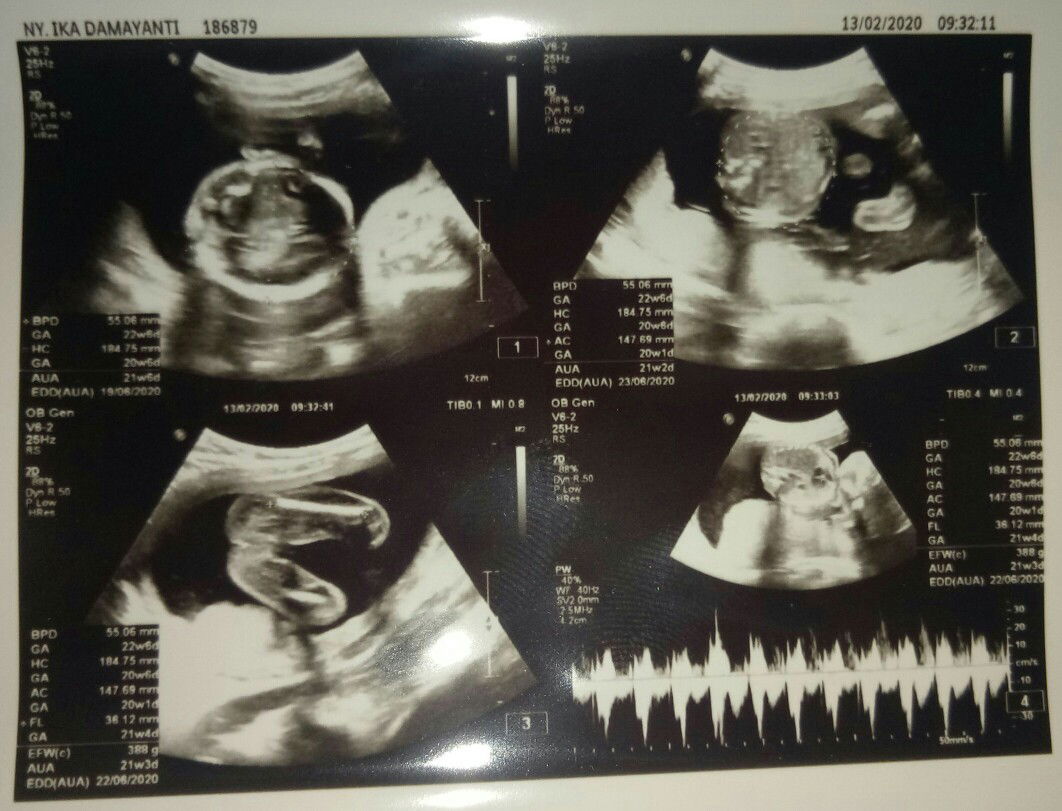

22week

Bismillah alhamdulilah Insyallah baby boy. Berbagi poto yu bunda2 kira2 jender nya sudah pada keliatan blum ya.